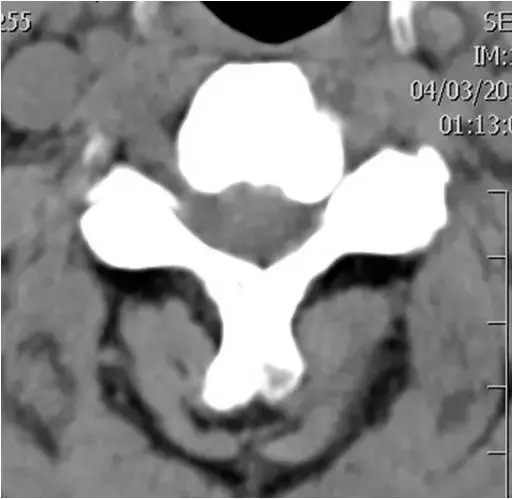

图23:下颈椎的轴向截面。广泛的骨赘形成和右钩椎关节肥大。硬膜囊颈髓的前部受压。确定脊柱狭窄。

图24:下颈椎的轴向截面。骨窗。与图像23相同的患者和相同水平。广泛的骨赘形成和右钩椎关节肥大。硬膜囊颈髓的前部受压。确定脊柱狭窄。